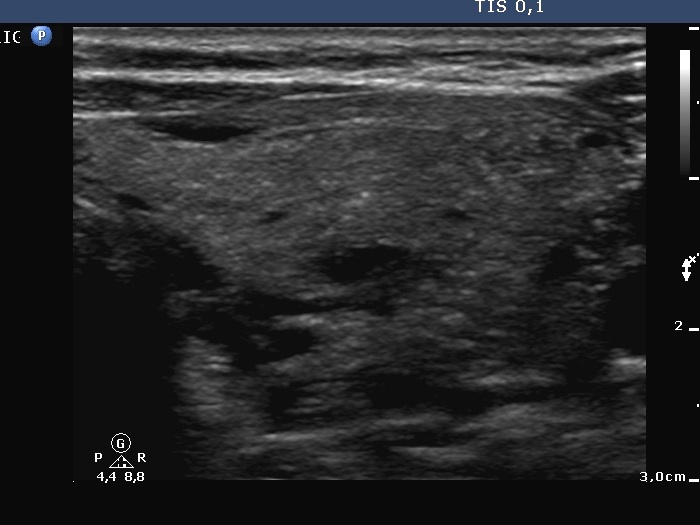

Lymph nodes - case conp 011

Follow-up investigation 17 months after the first visit (ultrasonographic picture 4)

Left lobe, transverse scan. The pattern is similar to that seen in the right thyroid.